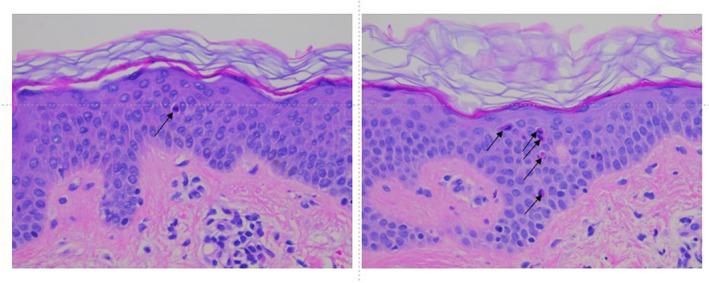

22 females were enrolled in the UVA study, and 10 females were enrolled in the UVB study. Skin chemiluminescence induced by UVA exposure was measured at baseline and after 2 weeks of daily topical application of the nature-based facial oil was evaluated in study 1. In study 2, UVB-induced erythema was measured after 8 weeks of twice-daily topical application of the nature-based facial oil to a photoprotected site followed by skin biopsy to evaluate sunburn cell formation. In both studies, the treatment response was compared to the response on untreated skin.

The nature-based facial oil significantly reduced skin chemiluminescence following UVA exposure, demonstrating antioxidant activity. The nature-based facial oil also significantly reduced erythema formation following UVB exposure and resulted in reduced sunburn cell formation in 66.67% of subjects.